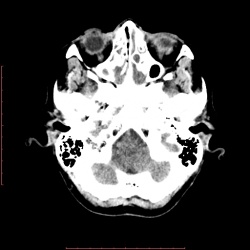

26.05.2014 - 10:14

Женщина 57 лет обратилась с жалобами на снижение зрения левого глаза. На УЗИ объемное образование левого глаза. Написал DDs меланома, ретинобластома..